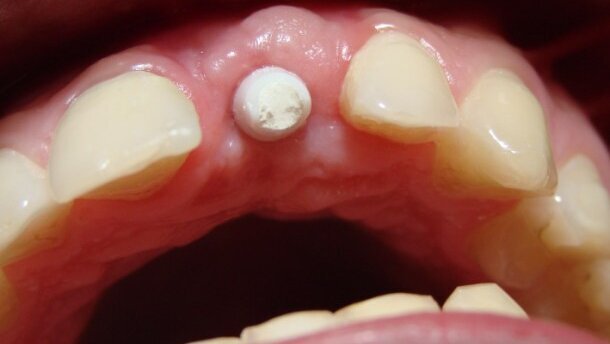

Ok. 14 miesięcy przed zgłoszeniem się do mojego gabinetu, u pacjenta przeprowadzono zabieg operacyjnego usunięcia zęba 21. Jako uzupełnienie tymczasowe wykonano protezę akrylową. Docelowo zaproponowano pacjentowi uzupełnienie braku 21 mostem PROCERA® 11 0 22, z uwagi na niedobór tkanek twardych i miękkich, jaki powstał po zabiegu (położenie 21 przedstawiono na rycinach 0-000) oraz relatywnie szybką możliwość uzupełnienia braku klasycznym mostem. Wspomniano też o leczeniu implantologicznym. Pacjent wybrał drugi wariant i został skierowany do mojej praktyki celem określenia możliwości wykonania takiego leczenia.

W etapie I z podniebienia (okolice 24/26) pobrano przeszczep łącznotkankowy (zgodnie z procedurą). Powstały ubytek w podniebieniu uzupełniono materiałem JasonFleece®. Następnie w okolicy 21 rozwarstwiono tkanki miękkie (tzw. split thickness flap) i wszyto przeszczep (wg Tarnow D, Stappert Ch). W II etapie, ok. 4 miesięcy po wykonaniu rekonstrukcji tkanek miękkich, wykonano zabieg augumentacji okolic 21 (zgodnie z obowiązującymi standardami). Zastosowano materiały Maxresorb® + JasonMembrane®. Po ok. 7 miesiącach po zabiegu osadzono implant SEMADOS 3.25x13 zgodnie z protokołem chirurgicznym (etap III). W etapie IV (ok. 6 miesięcy od poprzedniego zabiegu) implant odsłonięto, dokręcono śrubę gojącą i dostosowano uzupełnienie tymczasowe. Po ok. 2 tygodniach od chwili odsłonięcia implantu wykonano wyciski metodą otwartą (transfery pick-up, masa Express XT w systemie Pentamix). Procedura rejestracji i przeniesienia zwarcia przebiegała rutynowo – wykorzystano artykulator Stratos 200 i łuk twarzowy Ivoclar-Vivadent. Pamiętając o oczekiwaniach pacjenta w zakresie estetyki uzupełnienia, zaplanowano pracę cementowaną – korona PROCERA® na łączniku indywidualnym z tlenku cyrkonu.

Gotową pracę poddano symulacji okluzyjnej w artykulatorze Stratoss 200. Kontrola w warunkach klinicznych wykazała, że uzyskano poprawne kontakty zwarciowe. Implantokoronę osadzono na Temp-Bond. Śrubę łącznika uprzednio dokręcono z zalecanym przez producenta momentem obrotowym, a głowę śruby łącznika protetycznego zabezpieczono Coltosolem. Pacjent zaakceptował estetykę wykonanego uzupełnienia protetycznego (Ryc. 1-6). Rutynowym kontrolom poddawany był co 6 miesięcy.

Stan kliniczny po 3 latach po zakończeniu leczenia ilustrują ryciny A-D. Kontrolne zdjęcie OPG (Ryc. E, F) pokazuje bardzo dobrą przebudowę przeszczepu kostnego – praktycznie nie widać różnicy w strukturze kości).